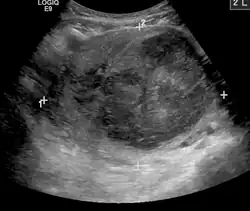

A very large (9 cm or 3.5 in) fibroid of the uterus causing pelvic congestion on US

Chronic pelvic pain

Veins have one-way valves that help blood flow toward the heart. If the valves are weak or damaged, blood can pool in veins, making them swell. When this happens near the pelvis, it is called pelvic congestion syndrome, which can lead to chronic pain beneath the level of the belly button.

Pelvic congestion syndrome usually affects women who have previously been pregnant, because the ovarian veins and pelvic veins had widened to accommodate the increased blood flow from the uterus during pregnancy. After the pregnancy, some of these veins remain enlarged and fail to return to their previous size, causing them to weaken and allowing blood to pool.[42]

An interventional radiologist can offer a minimally invasive treatment option for pelvic congestion syndrome: ovarian vein embolization

Ovarian vein embolization is a same-day treatment which takes place in an interventional radiology suite. The interventional radiologist gains access through a large vein in the groin, called the femoral vein, by using a small catheter, which is a flexible tube like a strand of spaghetti. The catheter is moved through the vein to the enlarged pelvic veins, allowing the introduction of embolic agents, which are medications that cause the vein to seal off and relieve the painful pressure.[43]

This treatment can be less expensive than surgery and is much less invasive.